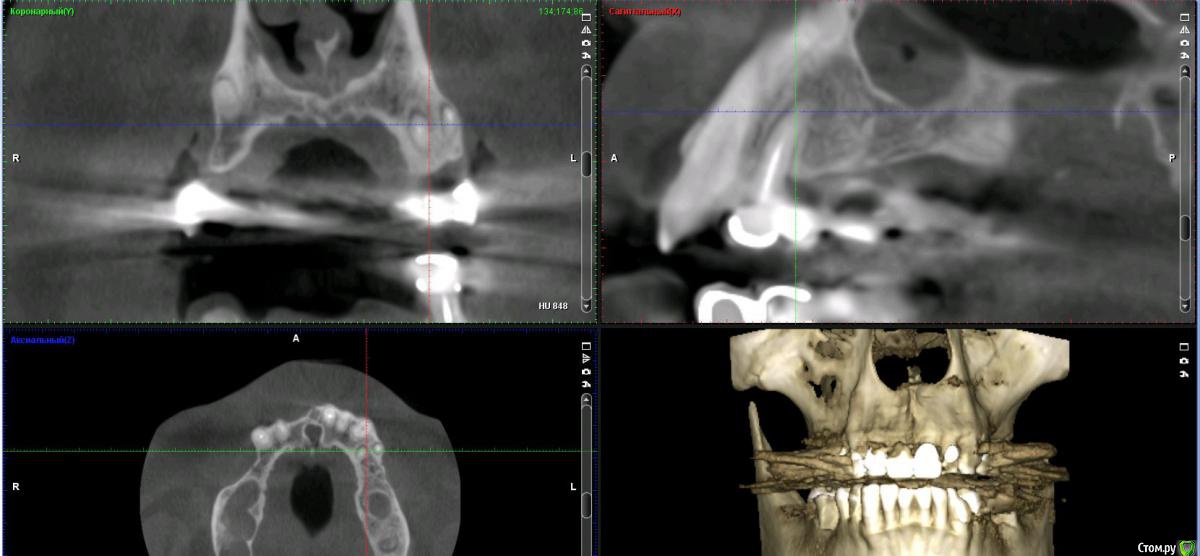

Дмитрий Л. Опубликовано 16 ноября, 2018 Поделиться Опубликовано 16 ноября, 2018 (изменено) Здравствуйте всем)Ситуация такая: старый мост 24-28. 28 симптоматичен, пациент принимает аб и противовосп. Имеется: - 24 перирадикулярные изменения (асимптомно)- 28 перирадикулярные изменения (обострение)- утолщение слизистой гайморовой (асимптомно)- невозможность имплантации в обл 26 (высота кости не позволяет) Пожелания пациента:- удаление 28 - желание сохранить мост - имплантация - нежелание носить съемную конструкцию Как планирую я:- перелечить 24, кальций 2-6 мес.- удалить 28- изготовить съёмник- выждать 4-6 мес. Повторить КТ, оценить гайморовую- имплантация 25, имплантация "где-то в обл 27" - всеми силами избежать синуса Мои грёзы:1. Ставить вблизи 24 - риск. Нужно лечить 24... реэндо... долго... может удалить? 2. Я верю, что причина хр гайморита - 28. Так ли это? Стоит ли ожидать позитивной динамики? 3. На сколько уйдёт кость после удаления 28 за 4-6 мес.? Её и так мало... Станет ли меньше? Графтить 28 не хочу. Там микробы. 4. Объём кости в обл 27-28 требует коротышку. Первыми приходят на ум Штрауман 6 мм (4 мм в кости, станет красиво) или ЭниРидж (бикортакально, скорее всего в пазуху на 1-2 мм). Нюанс в том, что я не работал этими системами... И коротышки не ставил. В общем придётся искать наборы, но это мои проблемы. 5. Итоговая конструкция: мост 25-27. При чём 27 имеет длину 4-6 мм, не слишком ли короткая дистальная опора? Вот спланировал приблизительно так... Надеюсь на отклик. Изменено 16 ноября, 2018 пользователем Дмитрий Л. Ссылка на комментарий

Irouil Опубликовано 16 ноября, 2018 Поделиться Опубликовано 16 ноября, 2018 (изменено) Без синуса это 2.5-2.8? Мне кажется надо синусить и нормально имплантировать, только с носом разобраться предварительно Апдейт: перечитал тс, 2.5-2.7. я бы, перед тем как стучать, сделал КТ соустья. Изменено 16 ноября, 2018 пользователем Irouil 1 Ссылка на комментарий

Nazim_NV86 Опубликовано 16 ноября, 2018 Поделиться Опубликовано 16 ноября, 2018 Эти гадания по кофейной гуще... Зачем вам лор? Сделайте два окна небольших. Через верхнее почистите синус. Нижнее - аугментируйте. 30 мин. Как запасной вариант. 1 Ссылка на комментарий

Nazim_NV86 Опубликовано 16 ноября, 2018 Поделиться Опубликовано 16 ноября, 2018 В районе 28 пока перфа зарастёт пройдет немало месяцев. Пока вырастет кортикалка. Толщина кости к этому времени станет вдвое меньше. А до этого закрытым методом поднять мембрану более 1мм будет непросто. Просто мысли.. 1 Ссылка на комментарий